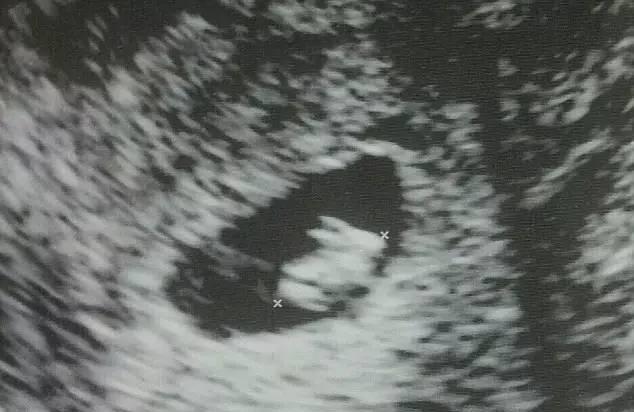

美国佛罗里达洲一名33岁的孕妇去医院超声检查时,在自己的超声影像上竟看到了一只惟妙惟肖的“兔子”,小兔子的长耳朵和四条腿清晰可见。 在日常工作中,你还看到过哪些有趣的超声图像,欢迎整合一下,投稿给我们哦~